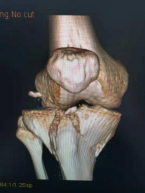

3.胫骨平台骨折